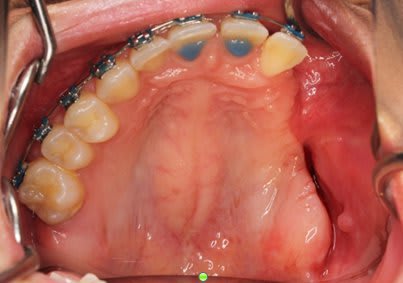

SI joint les photo intra buccal pre traitement et pendant traitement.

Comment expliquer vous le développement ce canting en frontal et de l'open bite en Postérieur ?

Qu'elle est la source du mal ?

Et après environs un ans de traitement

bah, il a répondu....le problème c'est la langue...

elle s'interpose entre les arcades, on la voit sur toutes les photos

problème de position et/ou associée avec une macroglossie

Photo 1 on met des brackets et fils un ans plus tard Photo 2

Une seul possibilité a ma connaissance qui explique le canting antérieur et l'open bite postérieur.

Bingo

Il y avait ankylose de la 22 mais pas des molaires.

Sa se devine ici car le fil est quasiment droit ce qui signifie que sa forme c'est exprimé presque complètement.

Le problème étant que si la forme du fil est correct sa position ne l'est pas.

La 22 étant ankylosé elle a fonctionné comme un point d’appui et a fait bouger tout le reste.

Dans ce cas c'est impressionnant car la dent ankylosé

- était mal positionné en début de traitement

- Qu'il n'y avait aucun dent dans le secteur postérieur pour limiter les effet.

Le fil rond pouvait tourner dans le slot de 22, vue qu'il n'y avait pas de dent en postérieure rien n’empêchait la rotation du fil et donc l’aggravation de la malocclusion.

La 21 qui était proche a était la plus affecté sa se voit bien sur les photo avec bracket, elle a subit une importante rotation dans le sens mesio distal et a était procliner. Son changement de position a eu un impacte sur 21 puis sur 11 ect ect , les effets devenant de plus en plus faible a mesure que l'on s'éloigne.

On a eu une important proclination de l'ensemble des incisive.

Mais encore une fois ce qu'il faut noter c'est le changement important au niveau de 21 avec un FIL PARFAITEMENT DROIT au niveau des incisives